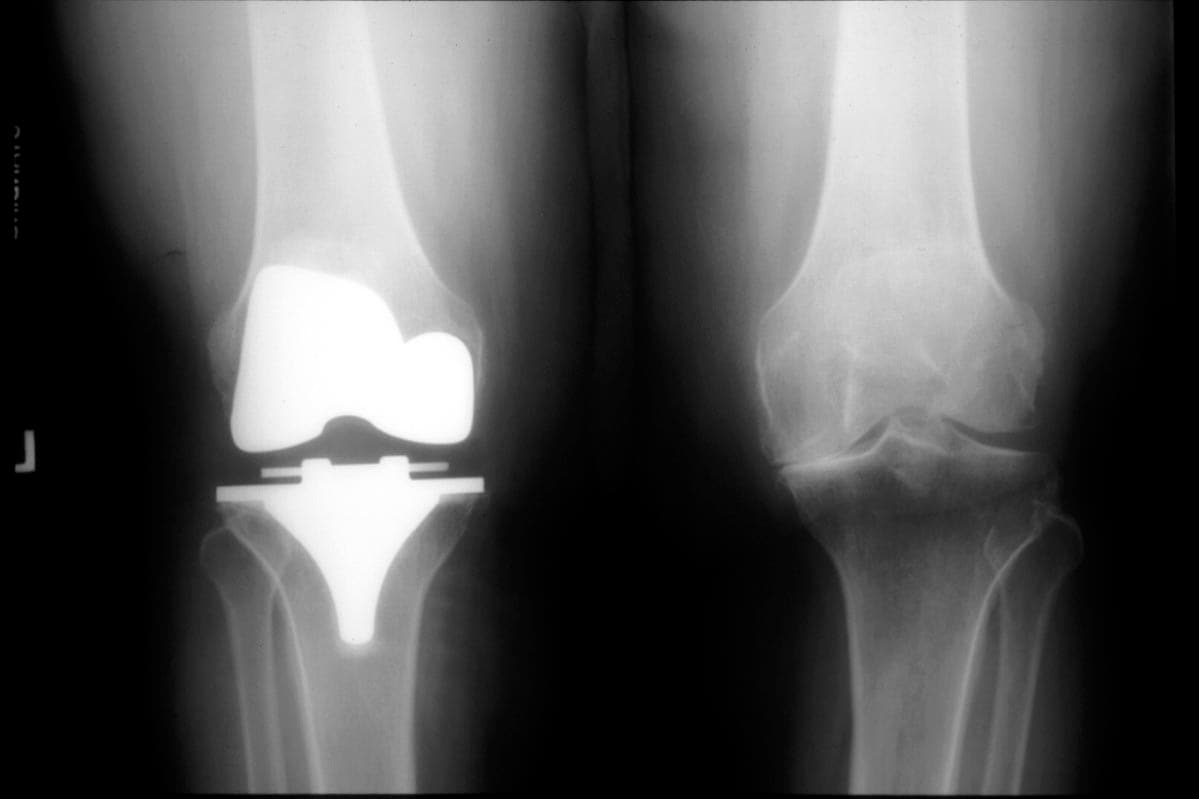

Problems With Zimmer Knee Replacements . Specialist lawyers at irwin mitchell have been contacted by worried patients who underwent knee replacement surgery with two. Unfortunately, some of the components used in zimmer knee replacements have suffered unanticipated high failure rates. Indications of loosening include radiolucent lines on imaging tests, which are large gaps between the device and bone. If you experience any pain or other problems associated with nexgen knee implants (for example a limp, inability to bear weight,. Problems associated with this implant can cause serious complications and patients can face the risk of loosening of their tibial component. A recalled knee replacement system has kicked off new product liability litigation in georgia after a recipient alleged portions of the. The largest knee implant maker in the world recently recalled thousands of its persona knee implants, leading the food and drug administration to issue a warning that the implants can loosen early and cause complications. While problems can occur, knee replacement, also called knee arthroplasty, typically has high success rates. The manufacturer, zimmer, says its recall is voluntary.

Specialist lawyers at irwin mitchell have been contacted by worried patients who underwent knee replacement surgery with two. A recalled knee replacement system has kicked off new product liability litigation in georgia after a recipient alleged portions of the. The manufacturer, zimmer, says its recall is voluntary. If you experience any pain or other problems associated with nexgen knee implants (for example a limp, inability to bear weight,. Unfortunately, some of the components used in zimmer knee replacements have suffered unanticipated high failure rates. The largest knee implant maker in the world recently recalled thousands of its persona knee implants, leading the food and drug administration to issue a warning that the implants can loosen early and cause complications. Problems associated with this implant can cause serious complications and patients can face the risk of loosening of their tibial component. Indications of loosening include radiolucent lines on imaging tests, which are large gaps between the device and bone. While problems can occur, knee replacement, also called knee arthroplasty, typically has high success rates.

Total knee replacement xray Zimmer NexGen arthroplasty, female Stock Photo Alamy Problems With Zimmer Knee Replacements If you experience any pain or other problems associated with nexgen knee implants (for example a limp, inability to bear weight,. The manufacturer, zimmer, says its recall is voluntary. While problems can occur, knee replacement, also called knee arthroplasty, typically has high success rates. Specialist lawyers at irwin mitchell have been contacted by worried patients who underwent knee replacement surgery. Problems With Zimmer Knee Replacements.